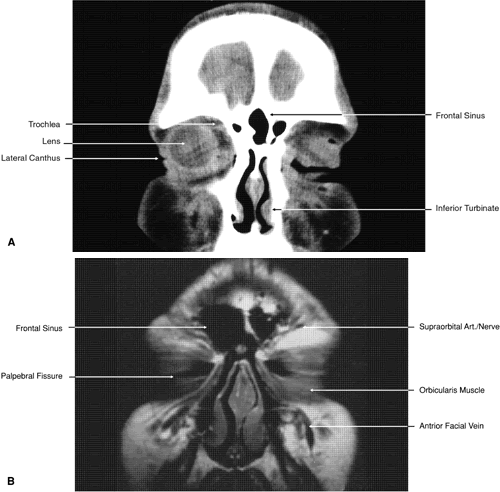

Fig. 17. Coronal images through anterior orbit. A. Computed tomography scan. B. T1-weighted magnetic resonance imaging.

Fig. 18. Coronal images through midglobe. A. Computed tomography scan. B. T1-weighted magnetic resonance imaging.

Fig. 19. Coronal images through midorbit posterior to the globe. A. Computed tomography scan.B. T1-weighted magnetic resonance imaging.

Fig. 20. Coronal images through orbital apex. A. Computed tomography scan. B. T1-weighted magnetic resonance imaging. C. Anatomic section of a cadaver head at the level of the orbital apex.

Fig. 21. Coronal images through optic canal. A. Computed tomography scan. B. T1-weighted magnetic resonance imaging.

Fig. 22. Axial images at the level of inferior orbit. A. Computed tomography scan. B. T1-weighted magnetic resonance imaging.

Fig. 23. Axial images at the level of midorbit. A. Computed tomography scan. B. T1-weighted magnetic resonance imaging.

Fig. 24. Axial images at the level of superior orbit. A. Computed tomography scan. B. T1-weighted magnetic resonance imaging.

Fig. 25. Axial images at the level of tendon of the superior oblique. A. Computed tomography scan. B. T1-weighted magnetic resonance imaging.

Fig. 26. T1-weighted magnetic resonance imaging; sagittal image through optic nerve.

Fig. 27. Coronal images through cavernous sinus and optic chiasm. A. T1-weighted magnetic resonance imaging through anterior chiasm. B. Computed tomography image through anterior chiasm. C. Computed tomography image through posterior chiasm. D. Computed tomography image through optic tract.

Fig. 28. Axial computed tomography image with contrast medium through cavernous sinus and pituitary gland.

Fig. 29. A. Axial computed tomography soft tissue image at the level of the base of skull. B. Axial computed tomography bone window image at the level of the base of skull.

Fig. 30. A. Axial T1-weighted image at the level of floor of orbit and trigeminal nerve. B. Axial T1-weighted image at the level of oculomotor nerve.

Fig. 31. Axial T1-weighted image through the cerebral peduncle at the level of oculomotor nerve.

Fig. 32. A. Axial computed tomography soft tissue image at the level of suprasellar cistern. B. Axial computed tomography soft tissue image at the level of thalamus. C. Axial T1-weighted image at the level of thalamus.

Fig. 33. Sagittal T1-weighted image of the brain through the interhemispheric fissure.

ORBIT AND PERIORBITAL STRUCTURES

The bony orbital and periorbital anatomy is best visualized with CT, whereas the soft tissue anatomy can be visualized with either CT or MRI. The orbital cavities are roughly shaped like quadrilateral pyramids parallel to each other medially and lying on one side with their apex facing posteriorly. The widest portion of the orbit is approximately 1.5 cm posterior to the orbital rim (see Fig. 2). On average the adult orbit is 40 to 45 mm deep, with the anterior orbit measuring 40 mm wide and 35 mm high. The interorbital distance in the normal adult is 25 mm. In contrast, the newborn orbit is more rounded, with a width and height of 27 mm, and the orbit of a 7-year-old measures 28 mm high and 33 mm wide.48 The orbital volume is approximately 30 mL, in comparison to the globe, whose diameter of24 mm gives it a volume of 6.5 to 7.0 mL.

The orbital roof is approximately triangular and is composed of the frontal bone anteriorly and the lesser wing of the sphenoid posteriorly. The roof is markedly concave, with the greatest degree of this concavity in the area of the equator of the globe (see Fig. 26). At the anterior and lateral portion of the orbital roof lies the lacrimal gland in the lacrimal fossa (see Figs. 18 and 23). This gland consists of a large orbital portion and a smaller palpebral portion. The orbital portion normally measures 20 × 12 × 5 mm, whereas the palpebral portion is about one third of this size.49 The supraorbital notch is at the junction of the nasal third and the lateral two thirds of the bony orbital margin (see Fig. 1). The trochlea of the superior oblique muscle is located 4 mm posterior to the orbital margin in the medial and anterior portion of the orbital roof (see Figs. 17, 24, and 25). Although usually a cartilaginous structure, it is occasionally partially or wholly ossified. It measures 4 × 6 mm and is firmly attached by connective tissue to the periosteum. The frontal bone portion of the orbital roof is extremely thin and like the orbital floor is subject to so-called blow-in fractures as well as to penetrating injury.50 The posterior portion of the roof is more substantial, measuring 3 mm thick. Except for the anterior portion of the orbit, the intracranial cavity lies directly superior to the orbital cavity (see Fig. 26). The levator muscle and the superior rectus muscle just inferior to it are present along the midportion of the orbital roof for all but its most anterior portion (see Fig. 26). The superior oblique muscle, after it changes direction at the trochlea, is present inferior to the anterior portion of the roof and inserts onto the globe inferior to the superior rectus muscle.

Anteriorly and medially, the frontal sinuses are superior to the orbit and lie between the two plates of the frontal bone. Occasionally, the ethmoid air cells are also found invading the orbital roof. The frontal sinus measures approximately 3 cm high,2.5 cm wide, and 2 cm deep. This is quite variable, and it is not unusual for one sinus to be considerably larger or smaller than the other or even completely absent. The two sinus cavities are separated by a bony septum that is usually deviated to one side. Medially the ethmoid air cells and nasal cavity lie below the frontal sinuses and are separated from them by a thin wall of bone. Superiorly and posteriorly the frontal sinuses are separated from the intracranial cavity and the frontal lobes by the thin frontal bone.

Immediately beneath the central portion of the orbital roof lies the frontal nerve, a branch of the ophthalmic division of the trigeminal nerve (see Fig. 18). Along with the trochlear nerve and lacrimal nerve, another branch of the ophthalmic division of the trigeminal nerve, it enters the orbit through the superior orbital fissure superior to the annular tendinous insertions of the extraocular muscles. The lacrimal nerve enters the orbit medial and superior to the superior orbital vein and travels laterally below the orbital roof and superior to the lateral rectus muscle to enter the lacrimal gland (see Fig. 24). The lacrimal artery arises from the ophthalmic artery lateral to the optic nerve and travels with the distal two thirds of the lacrimal nerve. The supraorbital and supratrochlear arteries branch from the ophthalmic artery superior to the optic nerve, passing medially to the superior rectus and levator muscles to accompany the supraorbital and supratrochlear nerves, the two branches of the frontal nerve, as they pass above the levator muscle. The supraorbital vein and artery accompany the nerve along the anterior two thirds of its course before exiting with it at the supraorbital notch. The other branch of the frontal nerve, the supratrochlear nerve, travels medially after separating from the frontal nerve at approximately the junction of the posterior one third and anterior two thirds of the orbit. The trochlear nerve diverges from the frontal nerve in the posterior orbit, passing medially below the orbital roof and above the levator and superior rectus muscles to enter the superior aspect of the posterior half of the superior oblique muscle.

The orbital floor is similar in shape to the triangular orbital roof and is composed of the maxillary, zygomatic, and palatine bones. Medially, the bony lacrimal canal containing the nasolacrimal duct lies just posterior to the inferior orbital rim (see Fig. 22). At this point the canal is formed by the maxillary and lacrimal bones. Just lateral to the bony canal is the origin of the inferior oblique muscle. Laterally, the floor is separated from the lateral orbital wall by the inferior orbital fissure, which begins lateral and inferior to the optic foremen and near the inferior aspect of the superior orbital fissure. It is approximately 20 mm long, ending 20 mm posterior to the lateral portion of the inferior orbital margin (see Fig. 14). The boundaries of the fissure are the maxillary and palatine bones medially, the greater wing of the sphenoid bone posteriorly, and the zygomatic bone laterally and anteriorly. Inferior to the orbital floor over most of its area is the maxillary sinus (see Figs. 5, 19, and 26). The bone of the floor is 0.5 to 1.0 mm thick, being thinnest at the inferior orbital groove and canal. The fragility of this bone is the reason it is commonly fractured during orbital trauma and the reason for orbital extension of sinus tumors. The ethmoid air cells are occasionally found within the orbital floor medially, and posteriorly there may be a sinus within the orbital portion of the palatine bone.48 The medial rectus muscle runs along the middle aspect of the floor until it inserts into the globe. It is in contact with the floor posteriorly, but anteriorly it is superior to the inferior oblique muscle (see Fig. 19).

The inferior orbital fissure is associated with several important soft tissue and bony structures. The maxillary division of the trigeminal nerve enters the fissure through the foremen rotundum and pterygopalatine fossa, dividing into the infraorbital and zygomatic nerves (see Figs. 20 and 21). This latter nerve separates into the zygomaticofacial and zygomaticotemporal nerves entering the zygomatic bone of the lateral orbital wall through small canals before exiting onto the face. The pterygopalatine fossa is bounded anteriorly by the pterygoid process of the sphenoid bone, the greater wing of the sphenoid, the maxilla, and the palatine bone (see Figs. 21 and 29). In addition to the maxillary division of the trigeminal nerve, it contains the pterygopalatine ganglion and its sensory, parasympathetic, and sympathetic branches and a portion of the maxillary artery. It communicates with the orbit by way of the inferior orbital fissure, the nasal cavity through the sphenopalatine foremen, and with the infratemporal fossa by way of the pterygomaxillary fissure. In addition to the foremen rotundum, sphenopalatine foremen, and pterygomaxillary fissure, the pterygoid and pharyngeal canals also enter into the fossa (see Fig. 29). After leaving the pterygopalatine fossa, the infraorbital nerve travels in the inferior orbital fissure a short distance before turning directly anteriorly into the infraorbital groove and canal within the maxillary bone. Finally it exits from the anterior surface of the bone 4 to 6 mm inferior to the midportion of the inferior orbital rim (see Fig. 19). The infraorbital artery, a terminal branch of the internal maxillary artery, accompanies the nerve along most of its course. Other branches of the maxillary division of the trigeminal nerve include branches to the pterygopalatine ganglion and the posterior, medial, and anterior superior alveolar nerves, which supply sensation to the upper teeth and gums.

The full extent of the orbital roof and floor as well as the superior and inferior rectus muscles and the levator muscle is best evaluated using sagittal views of the orbit (see Figs. 17 through 20, 26). Reconstructed images are generally too crude to provide detailed imaging of these structures. Coronal views of the orbit are excellent for showing the vertical dimension of the lateral and medial orbital walls and the horizontal dimension of the orbital roof and floor. This view is also important for showing the cross-sectional areas of the globe and orbital soft tissue structures, including the muscles, nerves, vessels, and orbital fat.

The lateral wall of the orbit is composed of the zygomatic bone anteriorly and the greater wing of the sphenoid bone posteriorly (see Fig. 14). Although the zygomatic bone also forms a portion of the orbital floor and is separated from the frontal bone and orbital roof by the frontozygomatic suture, posteriorly the sphenoid bone is prominently demarcated from the floor of the orbit by the inferior orbital fissure and from the roof of the orbit by the superior orbital fissure. The lateral wall is triangular and diverges at a 45-degree angle from the medial wall. Posteriorly it is slightly convex; anteriorly it is slightly concave; centrally it is flat. Posteriorly the sphenoid bone portion has a small protuberance of spine that separates the thin superolateral portion of the superior orbital fissure from the wider inferomedial portion. The lateral rectus muscle inserts onto this projection, which is formed in part by the groove containing the superior ophthalmic vein as it passes through the superior orbital fissure. Anteriorly the zygomatic bone has a small bony protuberance, the lateral orbital tubercle. This is just inside the lateral orbital rim and approximately 11 mm below the zygomaticofrontal suture. The levator aponeurosis, lateral canthal ligament, and check ligaments from the lateral rectus muscle insert onto this structure. A small lateral fat pad may also be present in this area.51 Anteriorly, where it is subjected to the greatest stress, the lateral orbital wall is quite thick. In contrast, posteriorly it is quite thin, only 1 mm thick.48 The temporal fossa and temporalis muscle are lateral to the lateral orbital wall for its anterior half, whereas the middle cranial fossa and temporal lobe are lateral to it for its posterior half. The lateral rectus muscle runs along the middle aspect of the wall until it inserts into the globe (see Fig. 23).

The superior orbital fissure separates the orbital roof from the lateral orbital wall and the lesser and greater wings of the sphenoid bone (see Figs. 13 and 14). The common tendinous ring (annulus of Zinn) of the extraocular muscles and the spine for the insertion of the lateral rectus muscle separates the fissure into a thin superolateral portion and a wide inferomedial portion (see Fig. 21). The fissure is approximately 22 mm long, and its superior end is 30 to 40 mm from the frontozygomatic suture.48 Directly posterior to the fissure are the middle cranial fossa and temporal lobe. Passing through the superior portion of the fissure above the tendinous ring are the lacrimal (cranial nerve V), frontal (cranial nerve V), and trochlear (cranial nerve IV) nerves, the superior ophthalmic vein, and the recurrent lacrimal artery. Passing within the ring are the superior division of the oculomotor nerve (cranial nerve III) and the abducens nerve (cranial nerve VI) laterally, the nasociliary nerve (cranial nerve V) and the inferior division of the oculomotor nerve medially, and the sympathetic root of the ciliary ganglion and the inferior ophthalmic vein, which on occasion may pass below the ring. The tendinous insertions of the lateral and inferior rectus muscles form the superior, lateral, and inferior portions of the ring in the area of the superior orbital fissure. There is no muscle tendon medial to the fissure. The medial border of the fissure is formed by a strut of bone from the lesser wing of the sphenoid bone, which separates it from the optic canal.

The medial wall of the orbit is formed by four bones: the frontal process of the maxillary bone, the lacrimal bone, the orbital portion of the ethmoid bone, and a small portion of the lesser wing of the sphenoid bone. Generally, this wall is parallel to the sagittal plane and is somewhat quadrilateral, unlike the other walls of the orbit. Superiorly and inferiorly this wall blends into the orbital roof and floor (see Fig. 14). Anteriorly the wall contains the lacrimal sac within the lacrimal fossa. This is formed by portions of the lacrimal and maxillary bones. The fossa is bounded anteriorly by the anterior lacrimal crest and posteriorly by the posterior lacrimal crest. The anterior lacrimal crest blends into the inferior orbital rim. Inferiorly the lacrimal fossa turns into the bony nasolacrimal canal, which exits beneath the inferior turbinate bone approximately 4 cm posterior to the opening of the nares (see Figs. 14 and 17). This structure is bounded by parts of the lacrimal, maxillary, and inferior turbinate bones. The fossa measures approximately 14 mm vertically and 5 mm anteroposteriorly, whereas the canal measures approximately 15 mm vertically.48 Medial to the lacrimal fossa, the anterior portion of the ethmoid air cells is present superiorly as well as the middle meatus of the nasal cavity inferiorly. Medial to the bony nasolacrimal canal is the middle meatus and inferior turbinate superiorly and the inferior meatus inferiorly.

The ethmoid portion of the medial wall contains the thinnest bone of the orbit (lamina papyracea). It is translucent to light and is only 0.2 to 0.4 thick (see Fig. 23).48 Because of its thinness, this area of the medial orbital wall is frequently prone to fracture. Anteriorly the medial wall is adjacent to the nasal cavity, middle turbinate, lateral wall of the nose, and the ethmoid sinus cavity. At its far posterior aspect the wall is adjacent laterally to the sphenoid sinus and medially to the optic canal (see Fig. 3). The superior oblique muscle runs along the superior aspect of the wall for most of its length before changing direction at the trochlea. The medial rectus muscle runs along the middle aspect of the wall until it inserts into the globe. The cribriform plate of the ethmoid bone is present medial to the superior aspect of the medial orbital wall at the point where the frontal and ethmoid bones join (see Figs. 5 and 24). Superior to the midportion of the cribriform plate and midway between the two medial orbital walls is a vertical portion of the ethmoid called the crista galli. Inferior to the cribriform plate and directly below the crista galli is the portion of the ethmoid bone forming the bony vertical aspect of the nasal septum (vomer bone). The anterior and posterior ethmoidal canals, which contain the posterior and anterior ethmoidal arteries, both branches of the ophthalmic artery, are present at the junction of the medial orbital wall and the orbital roof. The anterior canal is about 25 mm posterior to the anterior lacrimal crest, whereas the posterior canal is about 13 mm posterior to the anterior canal and about 8 mm anterior to the orbital opening of the optic canal.